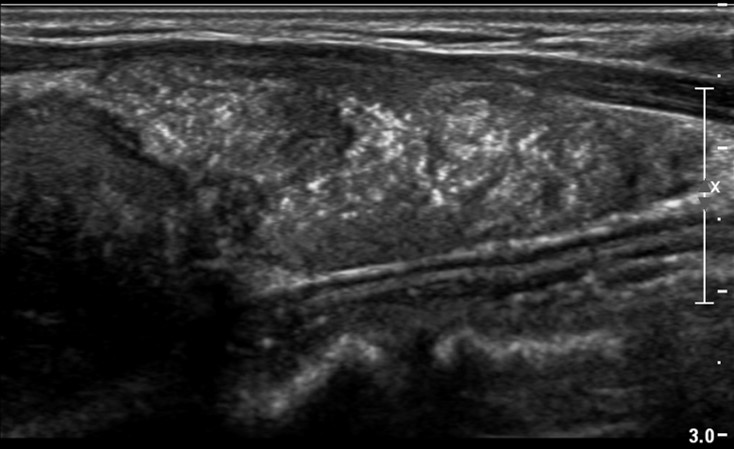

[353,] 42/F,검강검진상 발견된 갑상선 병변

Modality

US,CT,

Sae Rom Chung

,2025-10-25

진단은?

[Diagnosis]

Diffuse sclerosing subtype of PTC